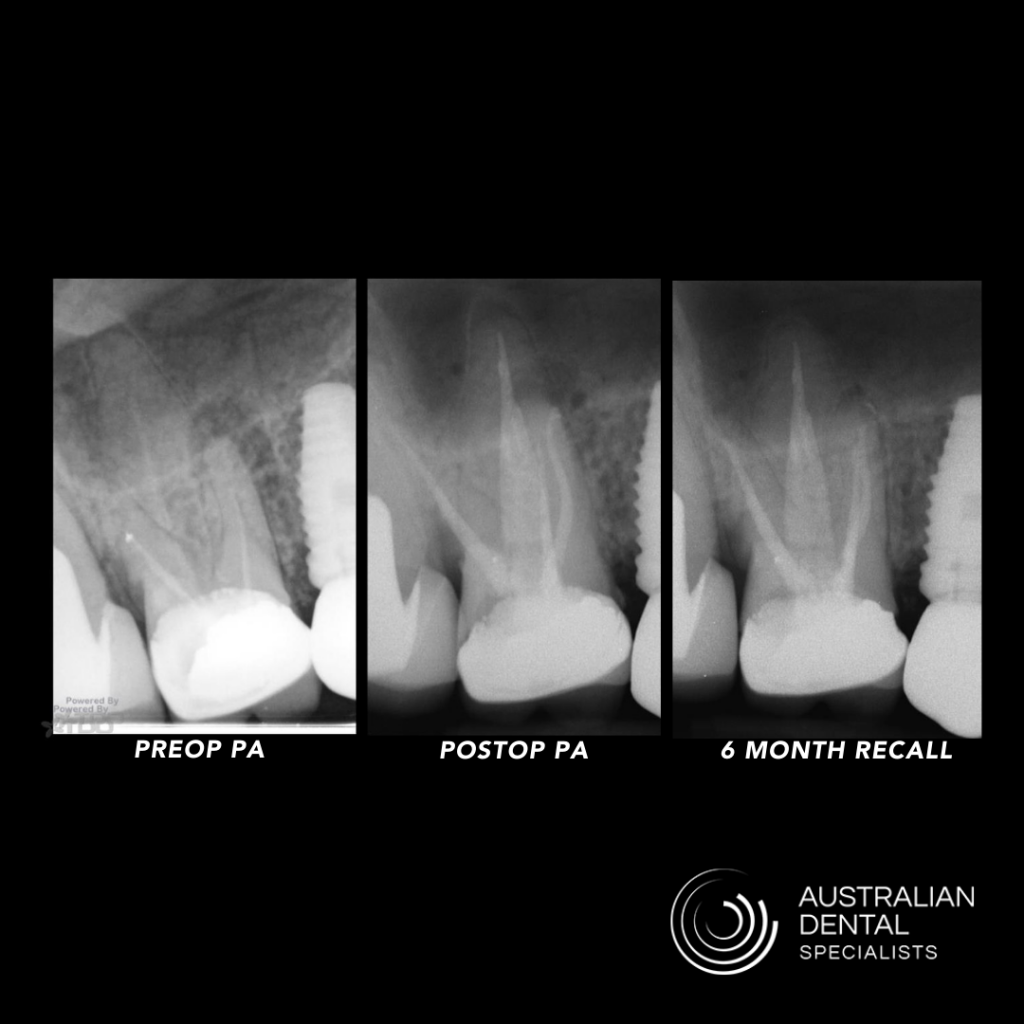

After that, the recall appointments started coming in, and the radiological healing was quick and comparable to those I had treated in multiple visits in the past. Over the last 18 months of practice, I’ve utilized the Waterlase on every single case that comes into my office. It’s so versatile that I can also use it for access preparation, cleaning sinus tracts, gingival augmentation, and crown lengthening.